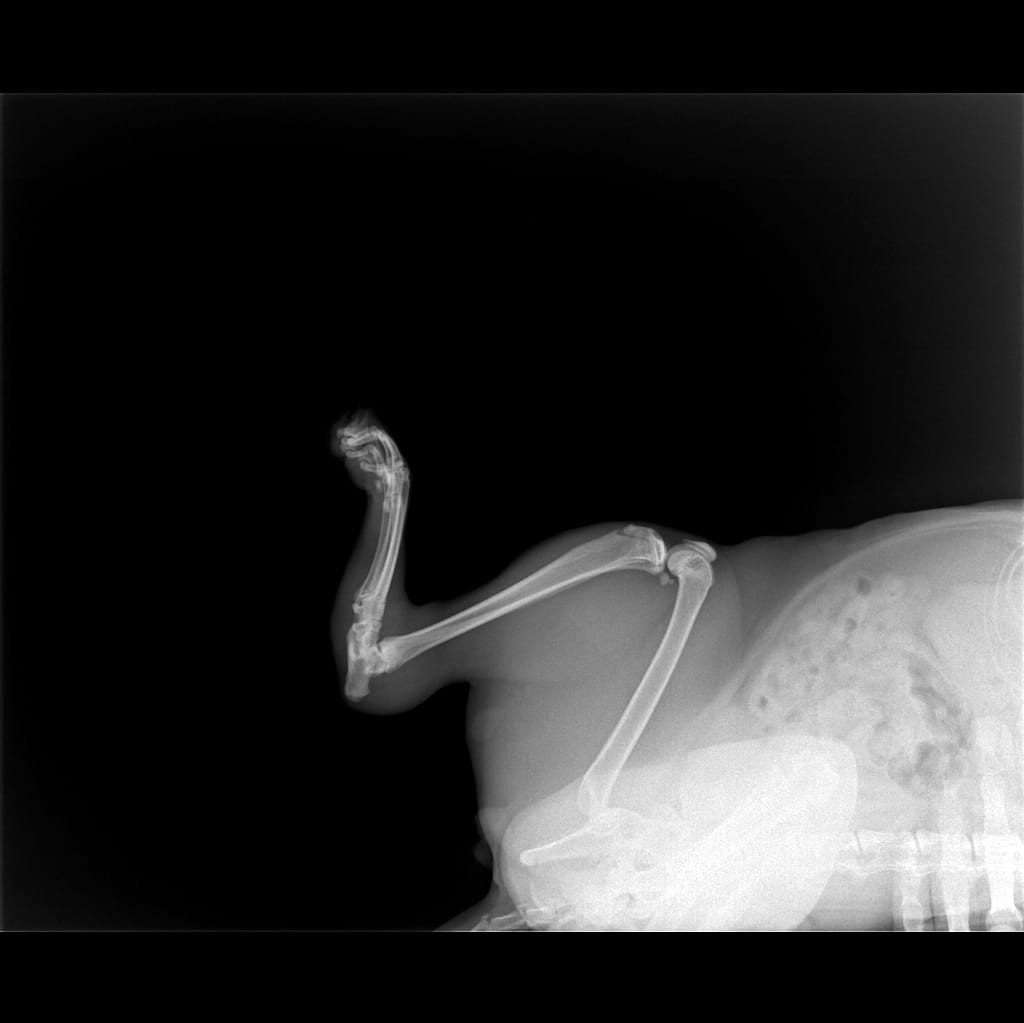

Добрый день позавчера кот 1.5 года прибежал в дом (дачный участок ) испуганный и мокрый его вытерли и он ушел спать . На следующий день почти не ходил (передвигался на 3 лапах , заднюю правую подгибал) , не ел не пил в туалет не ходил . Сегодня приехала забрала кота и отвезла в клинику где сделали рентген. Сказали трещина, прописали антибиотики ТК есть воспаление . Очень хотелось бы узнать мнение ещё одного специалиста ТК очень переживаю за кота . Сейчас стал более активный попил утром сходил в туалет по маленькому .

08 Июнь, 25

Здравствуйте. По рентгену  перелома с грубым смещением не видно, но можно предположить линейную трещину в области плюсневых костей или повреждение мягких тканей. Если кот не наступал на лапу в первые сутки, это нормально при болевом синдроме. Главное что он начал пить и писать, а значит рисков для почек и мочевого нет. Следите за аппетитом и если в течение 1-2 дней он не начнёт есть тогда обратитесь повторно. При ухудшении  потребуется контрольный рентген или УЗИ